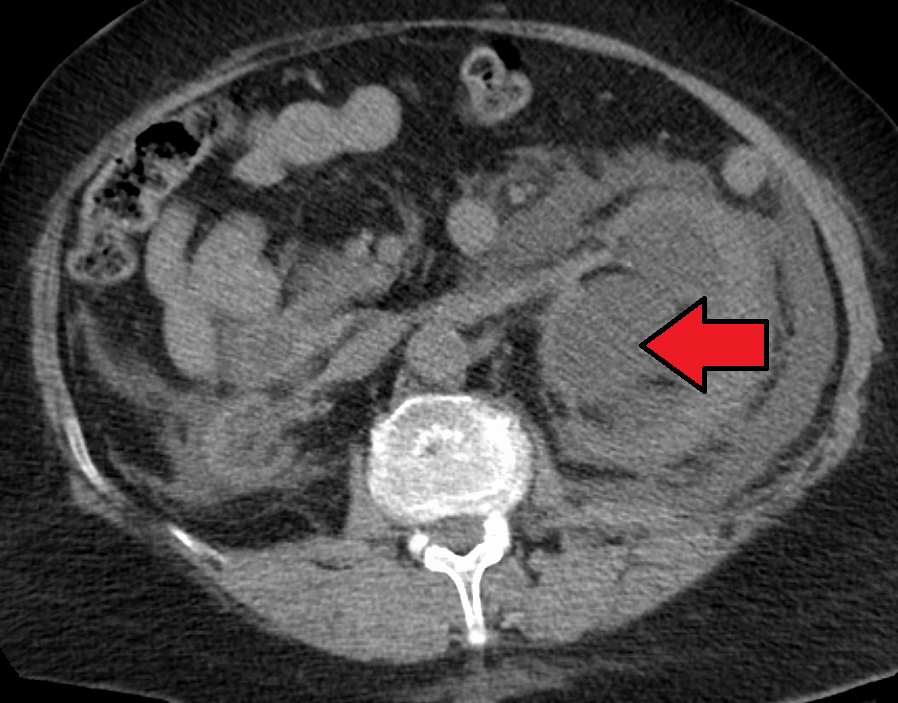

질병을 진단하려면 환자의 병력과 기타 신체 검사 정보를 알아야 한다. 이는 일부 영상 검사를 동반해야 한다. 일반적으로 초음파 검사를 사용하여 환자의 요로, 콩팥 등의 상태를 확인할 수 있다. 또한 CT 스캔과 MRI는 요로 및 폐쇄를 보다 명확하게 보여줄 수 있다.[8]

정맥 신우 조영술(IVU), 신장 초음파 검사, CT, MRI 등의 영상 검사도 중요하다. 초음파 검사는 요관과 신장을 시각화하고 수신증 및 수뇨관증 유무를 확인하는 데 유용하며, IVU는 막힘의 해부학적 위치 평가에 유용하다. 순행 또는 역행 신우 조영술은 IVU와 유사한 소견을 보이면서 치료 옵션도 제공한다. 실시간 초음파와 도플러 초음파 검사는 혈관 저항 검사와 함께 폐색이 요로 기능에 미치는 영향을 파악하는 데 도움이 된다.[12]

신 산통(소변에 혈흔이 섞인 옆구리 통증)의 초기 검사는 나선형 또는 헬리컬 CT 스캔이다. 이는 소변 흐름 폐색 여부와 다른 신장 기능도 보여준다. CT는 대부분의 결석을 확인할 수 있어 초기 검사로 흔히 선택되지만, 임신과 같이 방사선 노출을 피해야 하는 경우에는 사용하지 않는다.[13][14] 우연히 발견된 산전 수신증의 경우, 첫 검사는 산후 신장 초음파 검사다. 산전 수신증의 많은 사례가 자연적으로 해결되기 때문이다. 출생 후 며칠 이내에 시행하지만, 너무 이른 검사는 경미한 수신증을 놓칠 수 있어 4~6주 후 추적 초음파 검사를 권장하기도 한다.[15] 배뇨 방광 요도 조영술(VCUG)은 방광 요관 역류나 후부 요도 판막 같은 해부학적 이상을 배제하기 위해 시행된다. 수신증이 심각하고 요관 신우 접합부(UPJ) 또는 요관 방광 접합부(UVJ) 폐색이 의심되면, MAG-3 스캔과 같은 핵 영상 검사가 필요하다.[13]